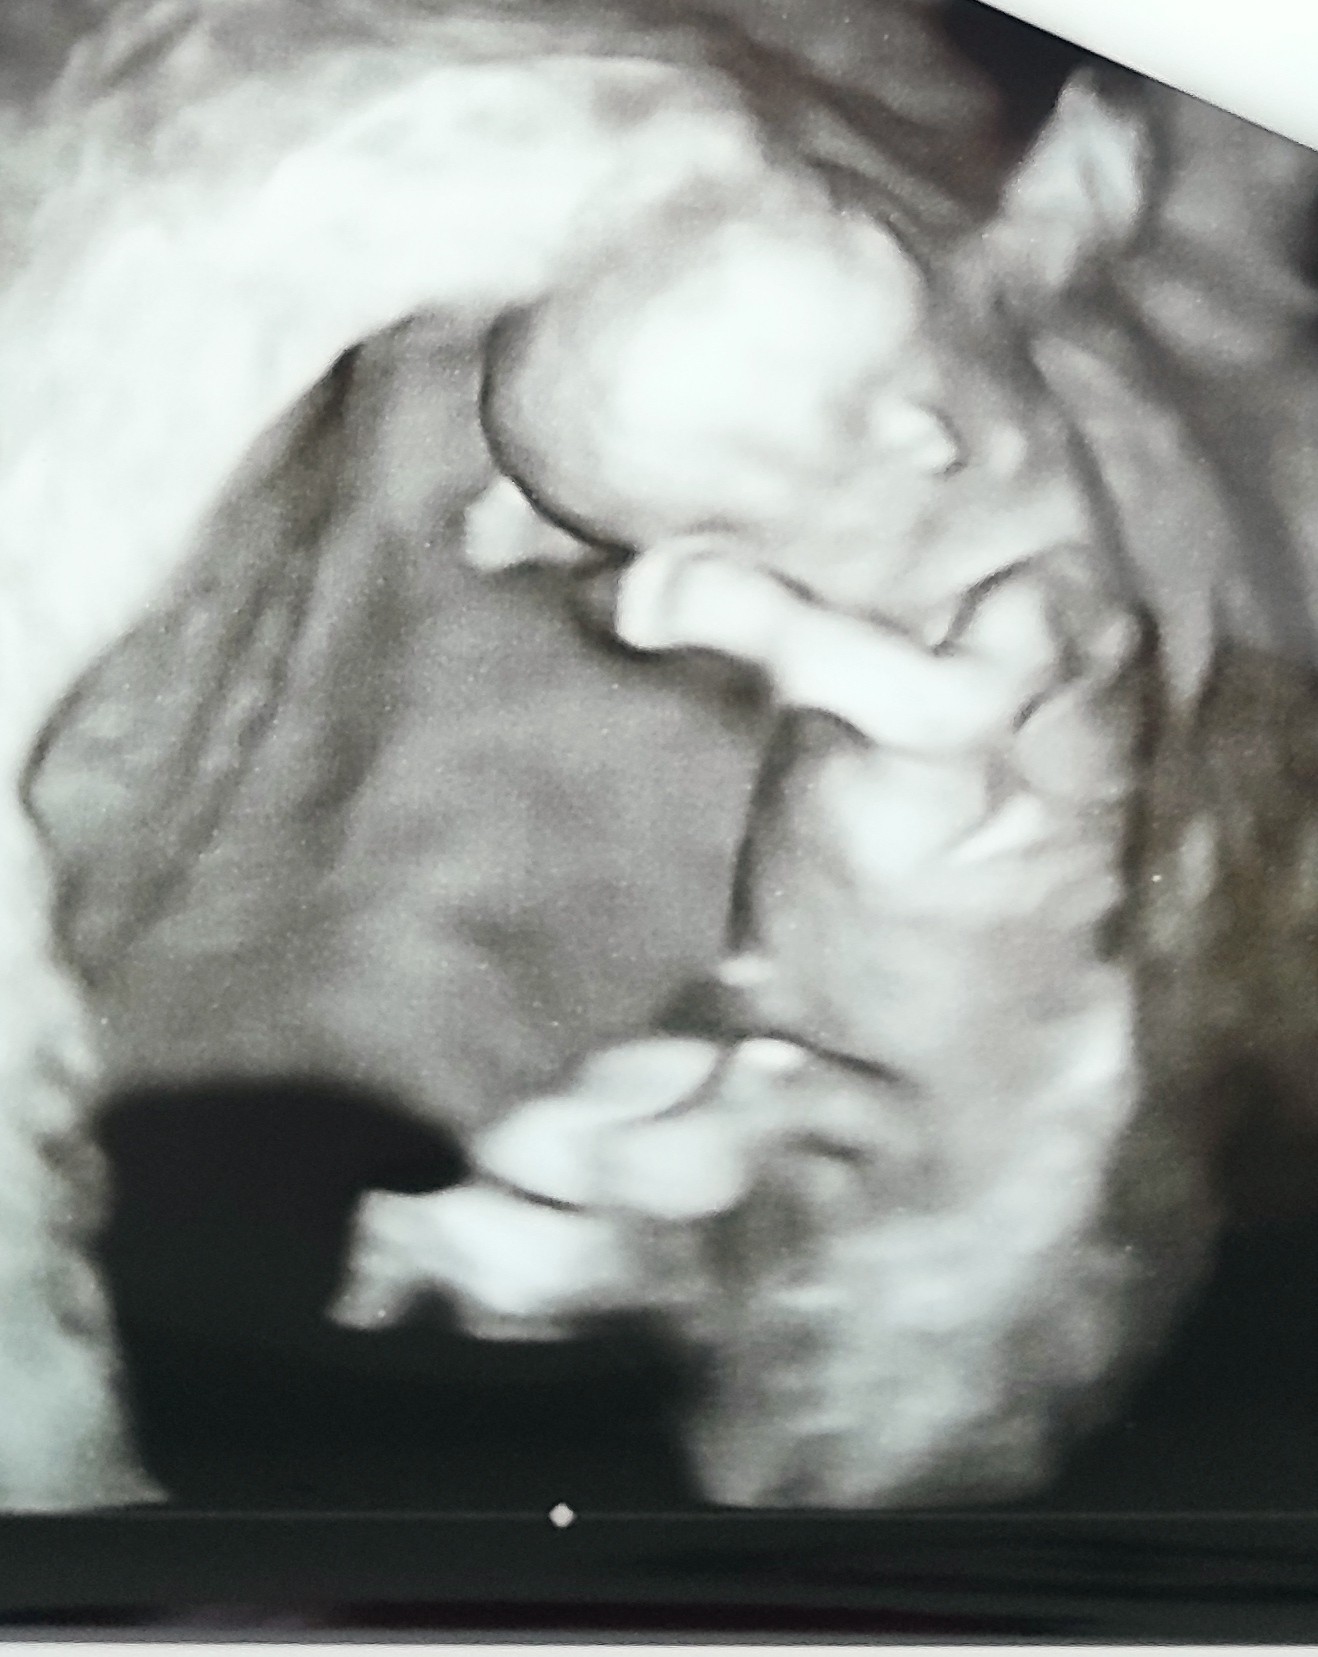

Fanka BB :)

Jak to przeczytałam to sama sie zestresowałamhej, gratuluję wizyt ☺☺☺ ja jutro mam prenatalne, dziś dzwonili żeby potwierdzić i wizyta bez osób towarzyszących. Stres już mam ogromny a co będzie jutro![]()

Bede trzymać kciuki! Ja prenatalne 9 sierpnia i tak czekam na nie... ale sie dłuży